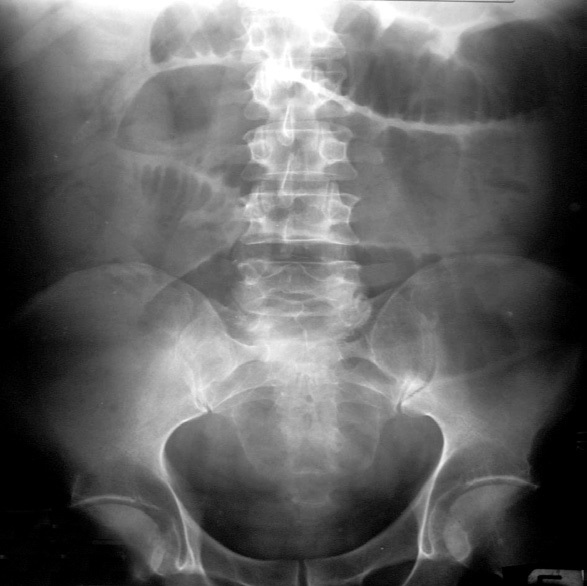

Erect x –ray abdomen:

Erect x-ray abdomen was done to look for free air under diaphragm and to look for obstruction

Xray Abdomen |

Multiple air fluid levels |

Abdominal radiograph

• Screen for other differential diagnosis and free air

• 45% sensitivity